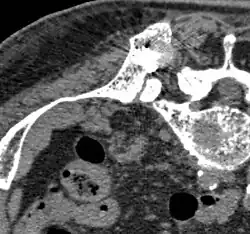

Métastase ostéocondensante d'un cancer de la prostate dans la hanche

Scanner d'une métastase d'un cancer de la prostate à gauche dans le pubis (à dr. sur l'image)

TEP de la même métastase au pubis

Image composite scanner/TEP de la même métastase